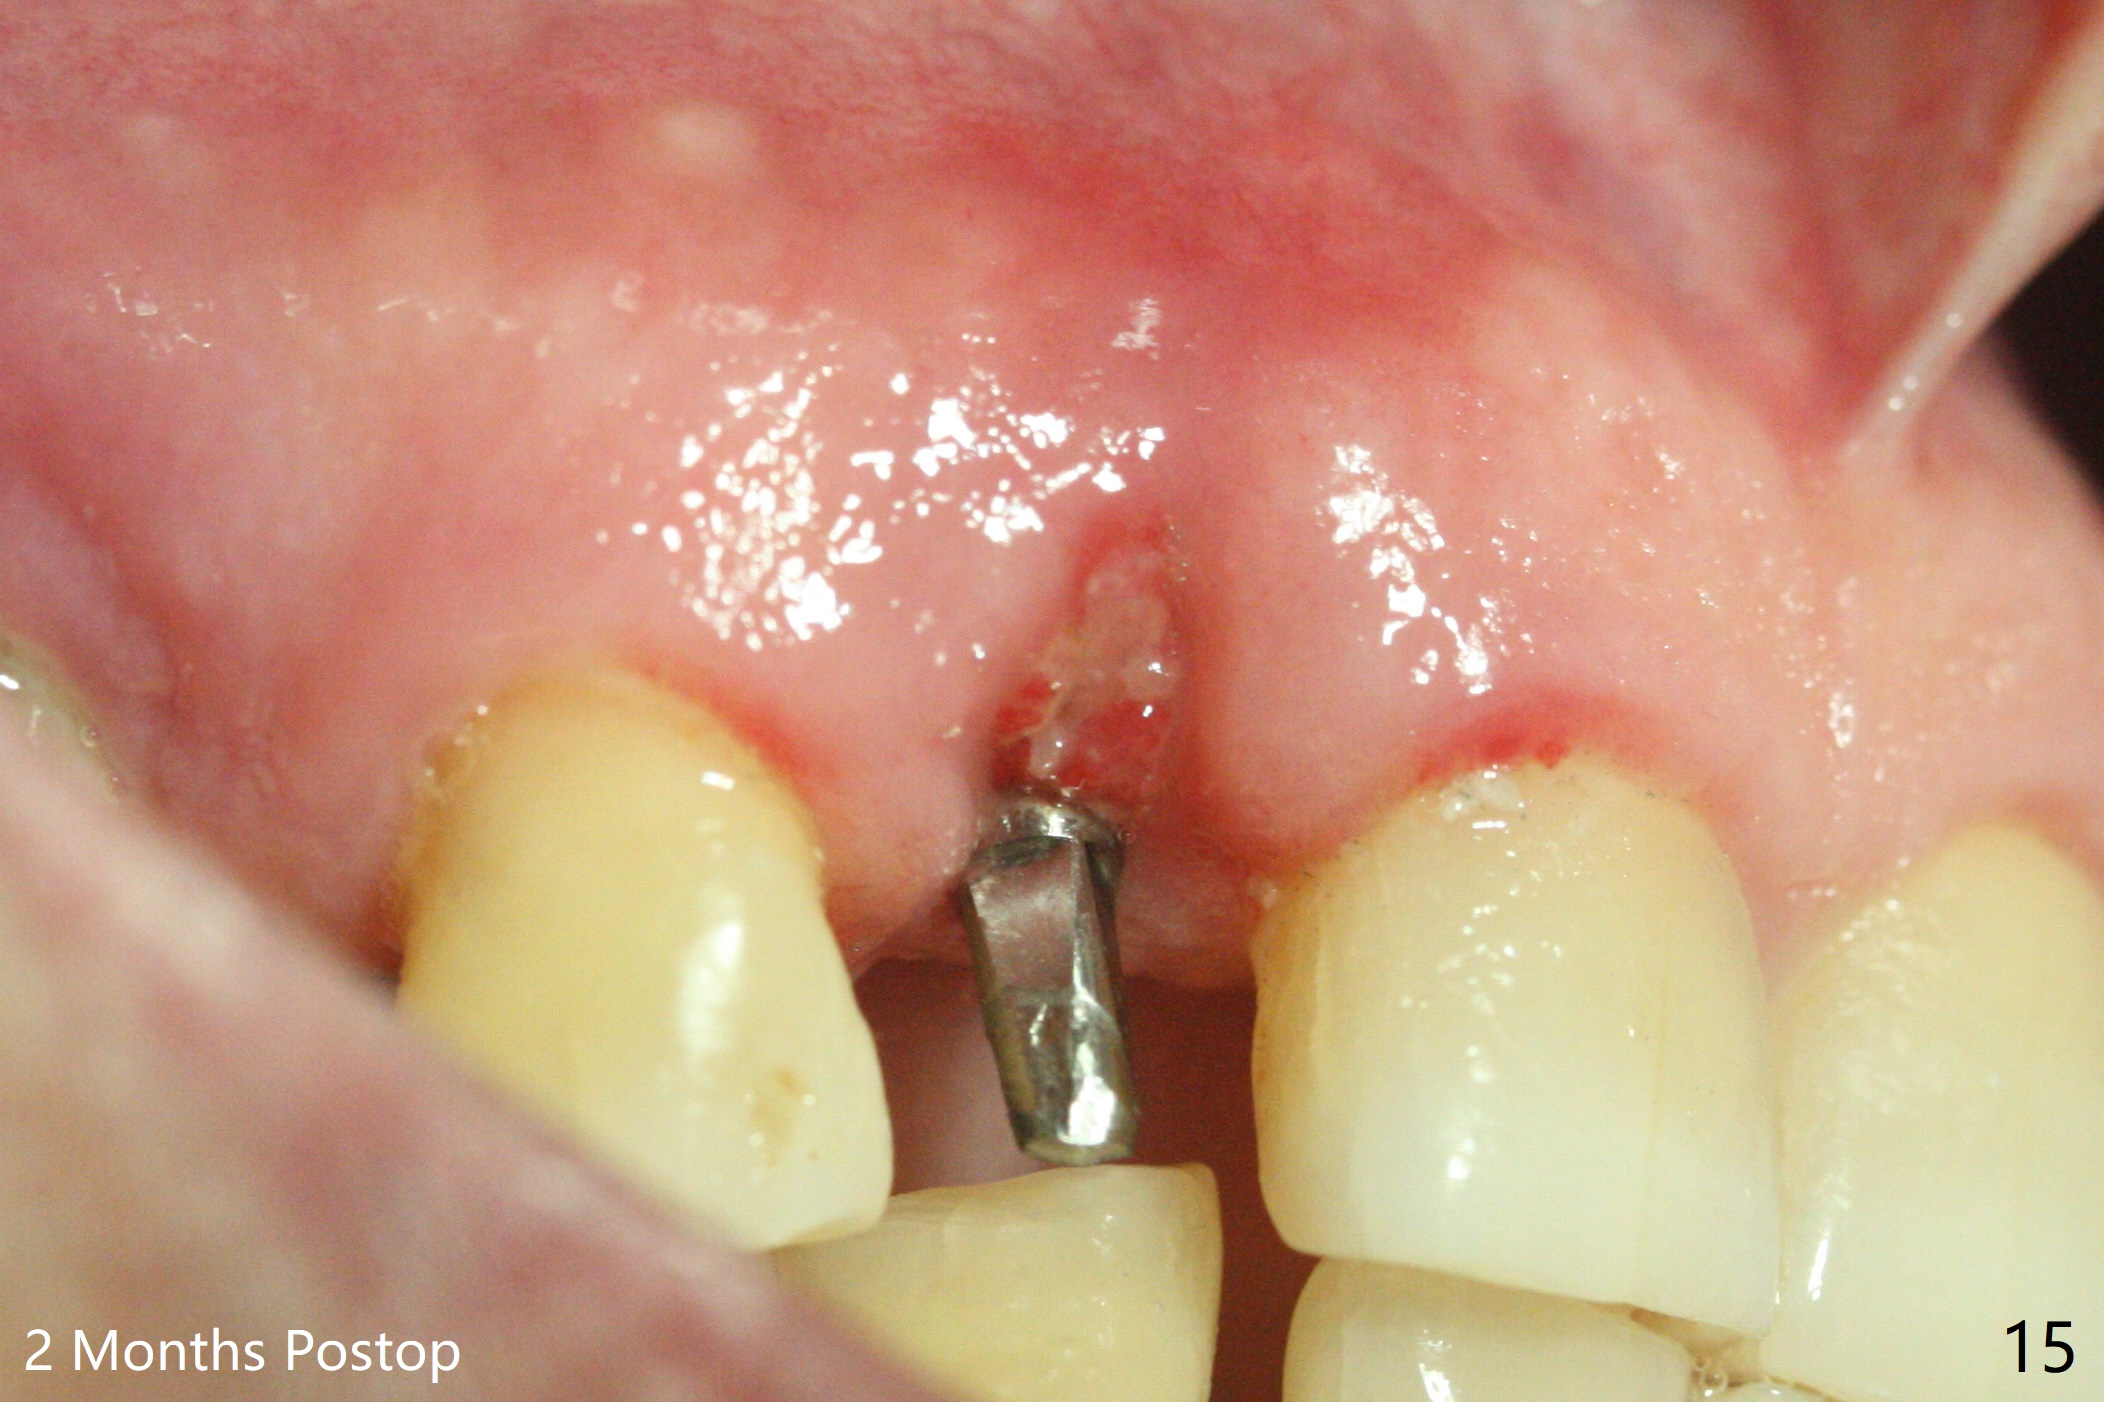

68岁男士右上2严重骨质吸收,颊侧骨板缺失,术前牙龈退缩也十分明显(图一,二),术中对脆弱牙龈缘(图三:*)不应施加任何压力或者牵拉,更不能切开,保持最佳血供。按照术前设计,在牙槽窝腭侧钻洞(图四),植入2.5x15毫米一段式植体(扭力>35Ncm),基台特长(牙龈厚,图五)),基台位于合适修复位置(图六),4-5毫米螺纹颊侧暴露(图七:*)。植骨(图八(CT冠状切面(拔牙后:黑色)):箭头)前,将PRF膜(白线)一头(a)插入牙槽窝颊侧,另外一头(图八,九:b)放置颊侧牙龈颊侧。然后填入粘性骨粉(图九:S;图十四:*),将b头PRF膜往下翻,它末端事先冲一个洞(punch a hole using sterilized rubber dam punch),插入基台(图十(粉红色),十一),这样PRF膜不移位,牢靠地固定骨粉(图十(红圆圈),图十四:*),最后使用树脂敷料覆盖伤口(图十二,十三:A),同样需要基台(箭头,也就是一段式植体)固定,也就是没有即刻植体,就没有骨粉固位。术后两个月伤口缩小,肉芽组织生长(图十五)。撤除树脂敷料后,制作临时牙冠,半个月后唇侧植体有些暴露(图十六),嘱咐强化口腔卫生。